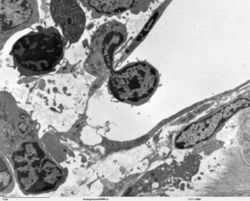

A transmission electron microscope image of an immune cell crossing from the bone marrow into the circulation